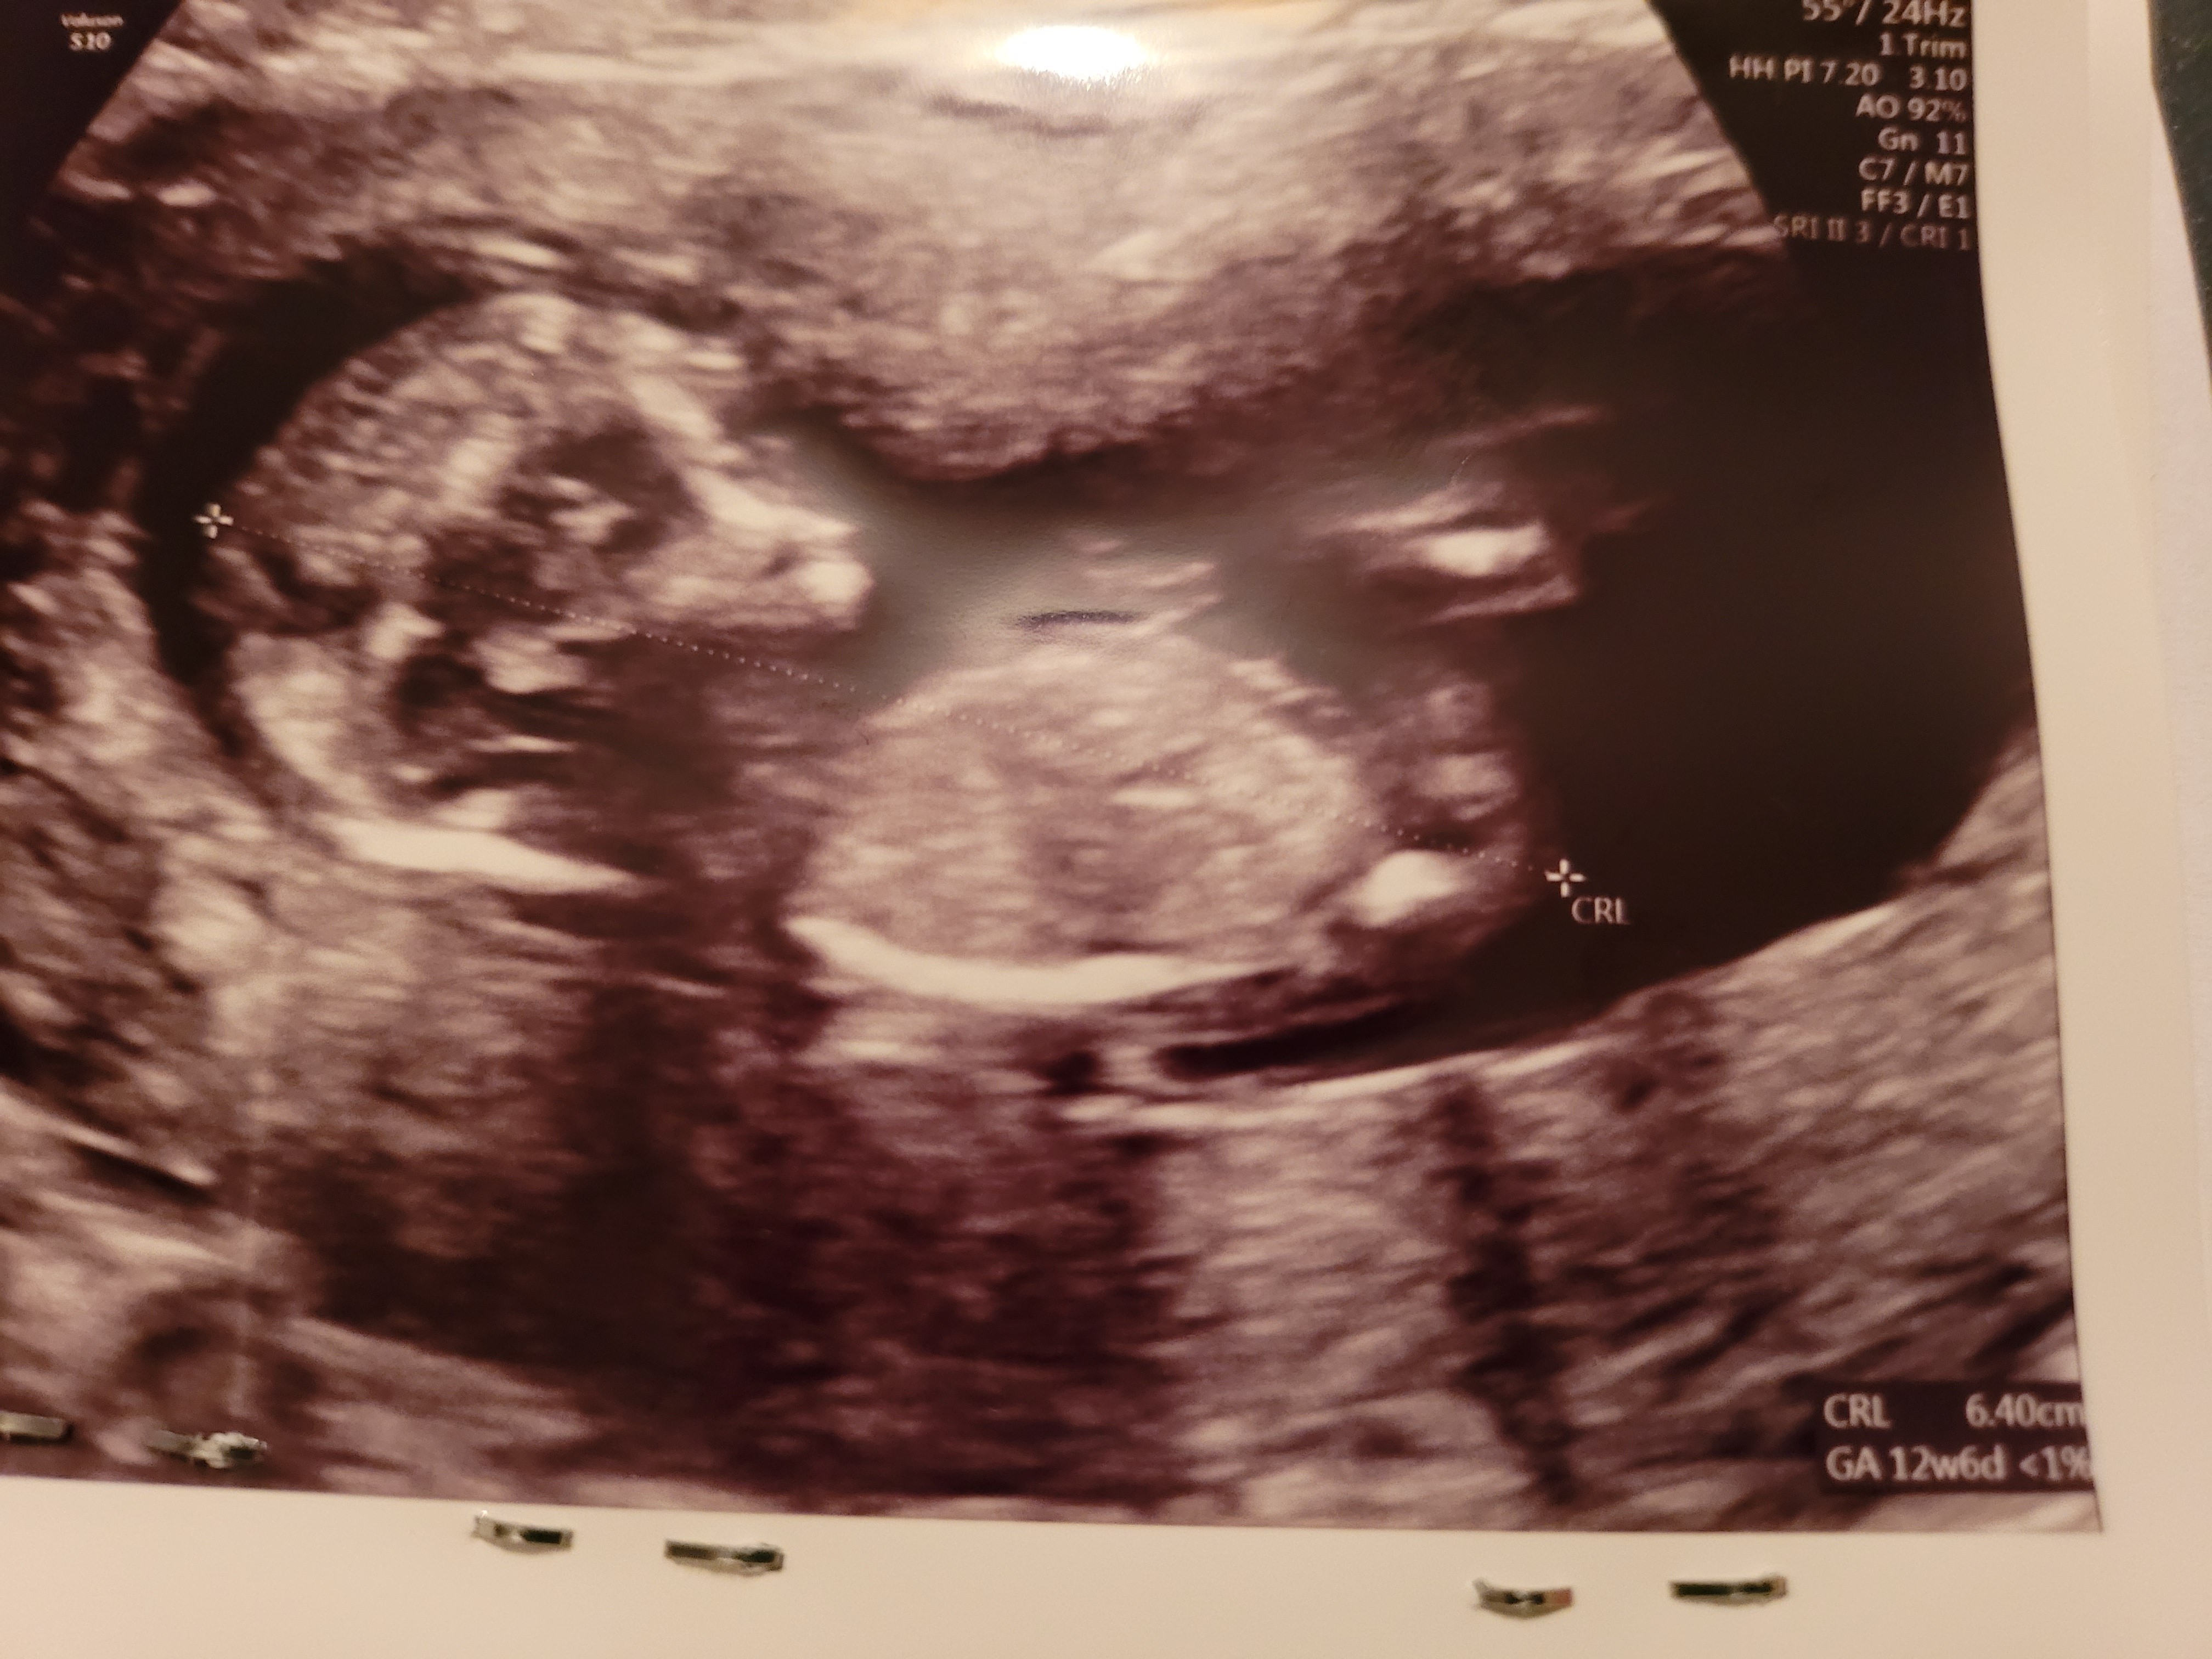

Wg Was dziewczyny będzie synuś,czy córeczka?Pozdrawiam

Dobrze strzeliłam?